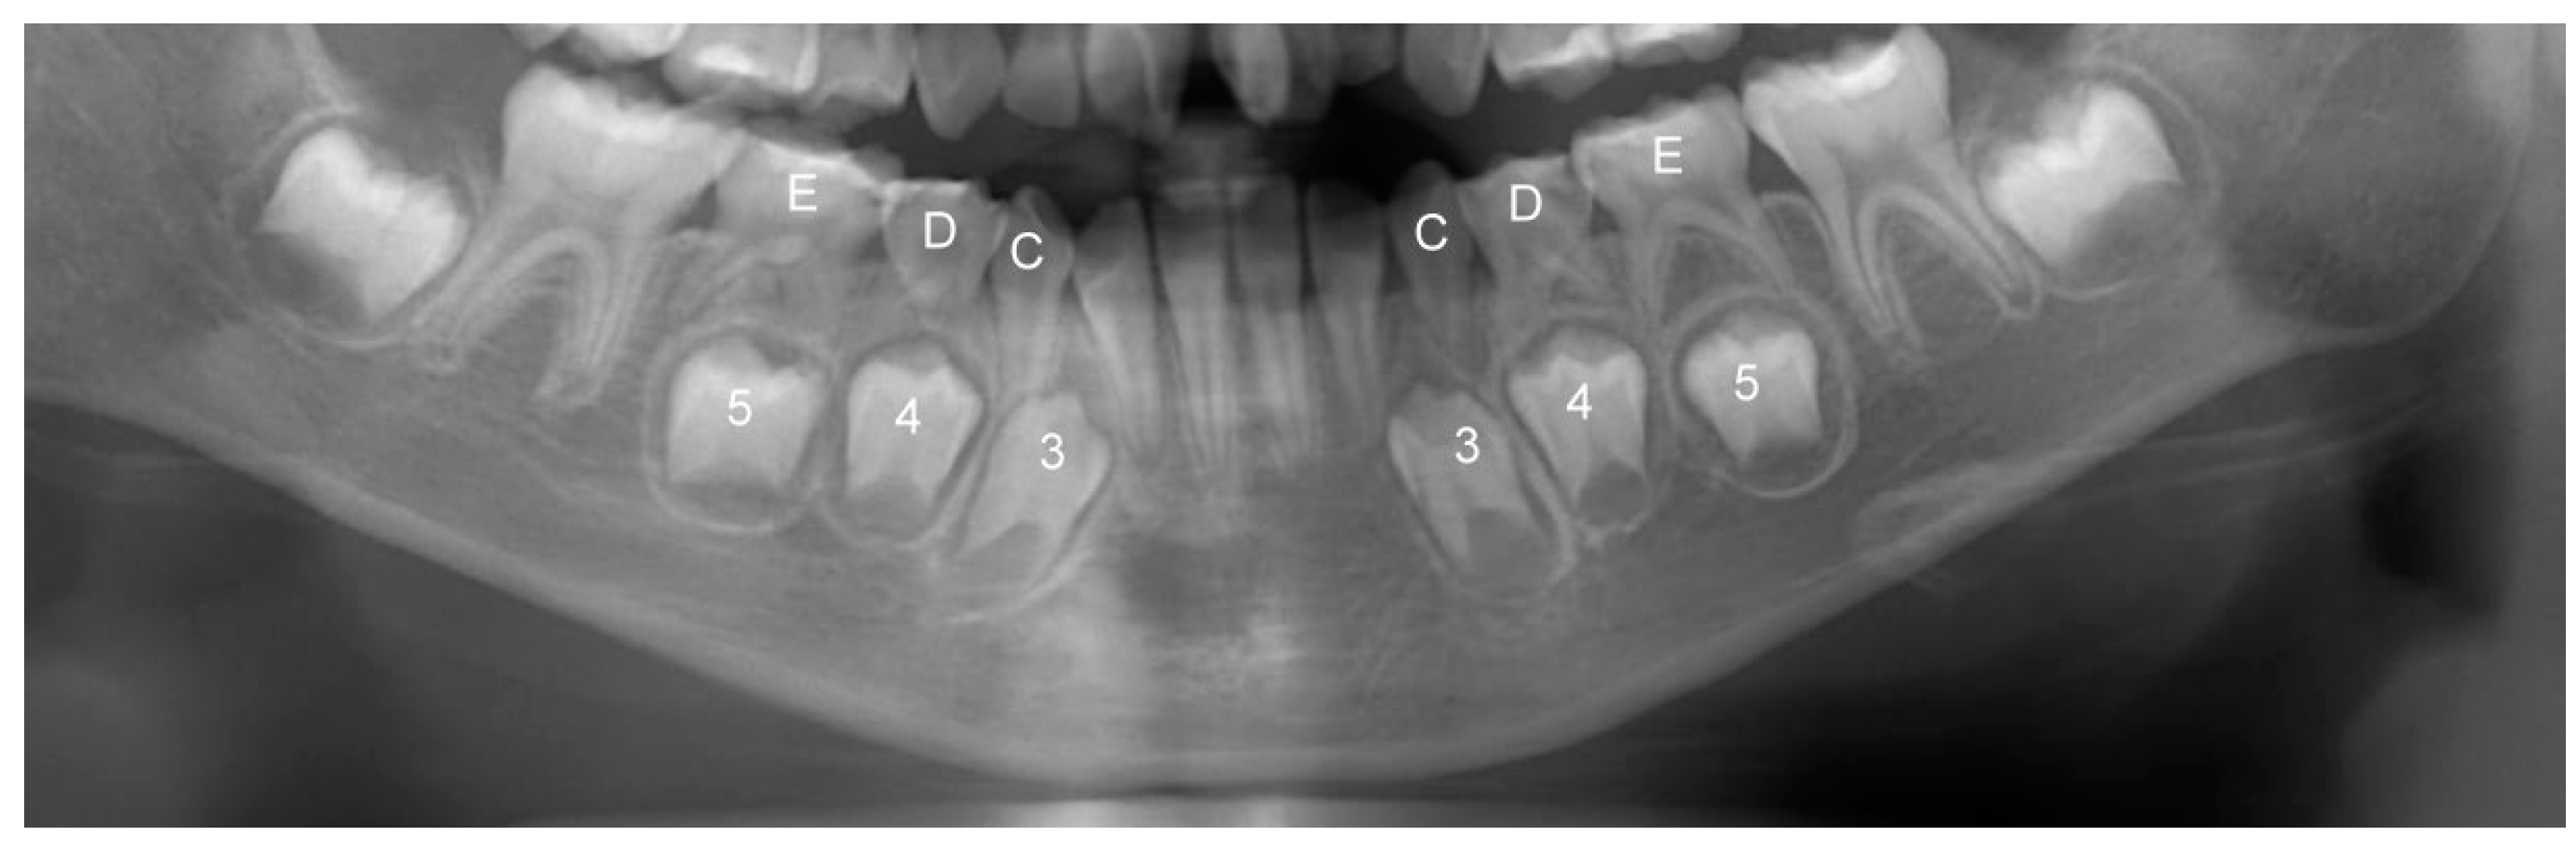

2.2. Digital Panoramic Scanning and Measurement of Leeway Space